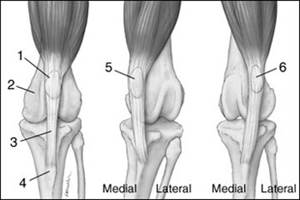

Коленный сустав схематично можно увидеть на рисунке. Здесь изображено нормальное положение связки относительно сустава, медиальное смещение и латеральное смещение.

При вывихе связка смещается так, как указано на среднем рисунке – в медиальном направлении, то есть внутрь.